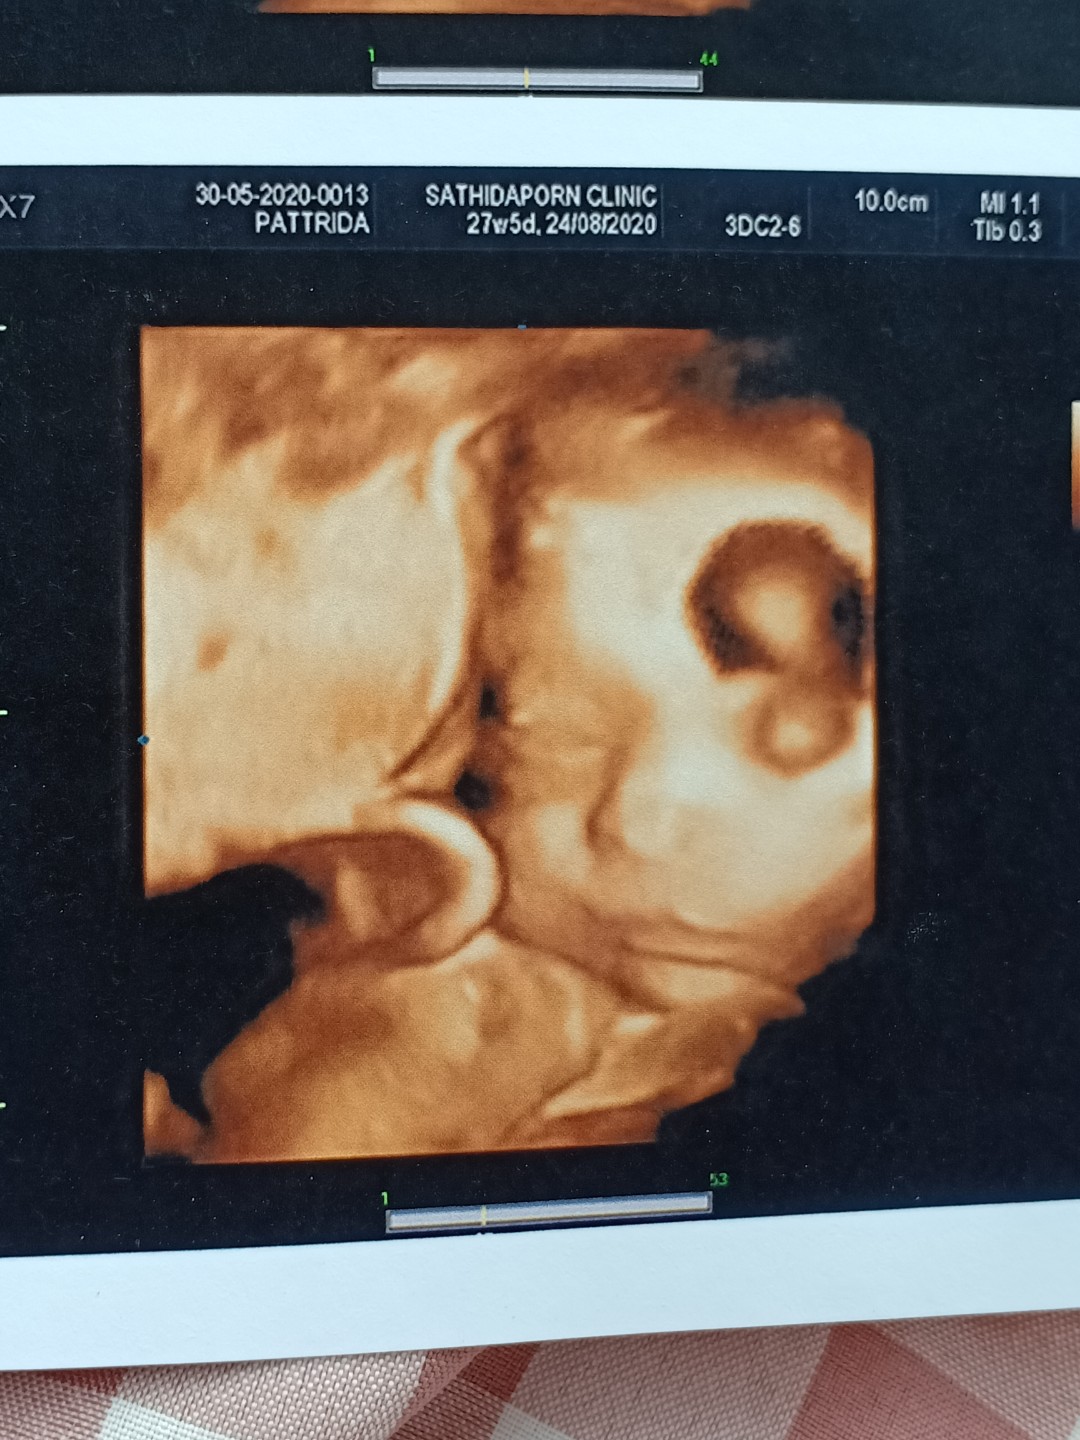

26/8/63ลูกสาวค่ะ